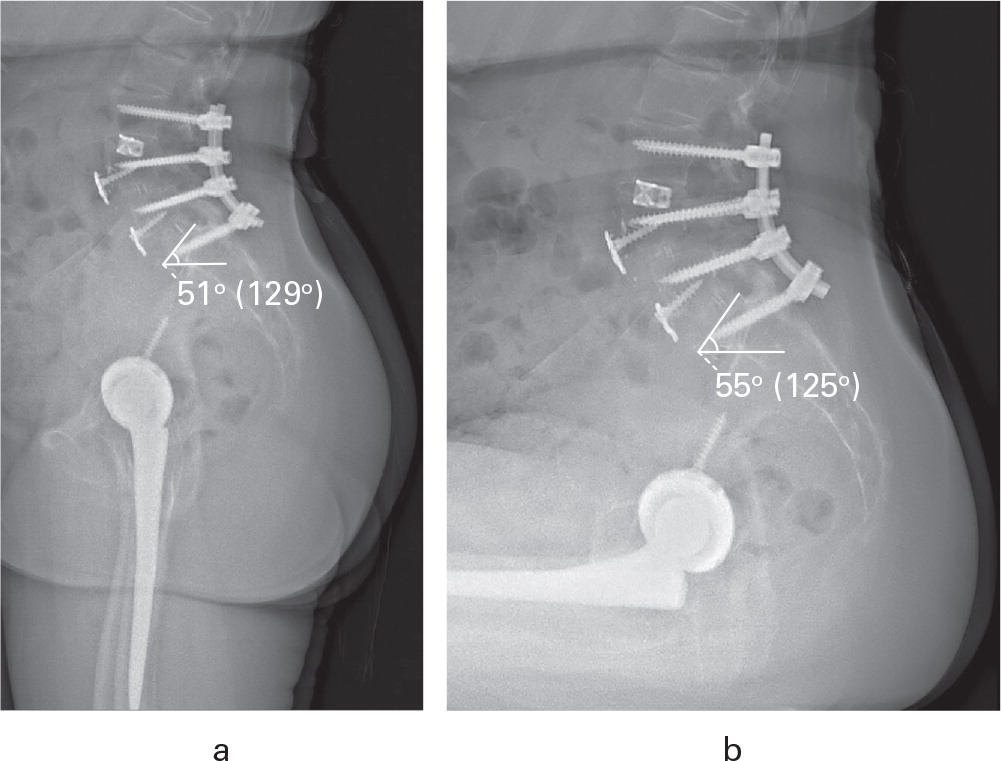

Los pacientes con patología de la columna que se someten a una artroplastia total de cadera (ATC) tienen un mayor riesgo de dislocación y revisión. El objetivo de este estudio fue determinar si el uso del sistema de clasificación Hip-Spine en estos pacientes daría como resultado una disminución de la tasa de luxación postoperatoria en pacientes con patología espinal.

Ésta es la serie más grande de la literatura que evalúa la relación entre la patología cadera-columna y la luxación después de una ATC y orienta el tratamiento adecuado. El sistema de Clasificación Cadera-Columna permite a los cirujanos realizar evaluaciones adecuadas antes de la operación y guía el uso de componentes de movilidad dual (DM) en pacientes con patología espinopélvica para reducir el riesgo de luxación en estos pacientes de alto riesgo.